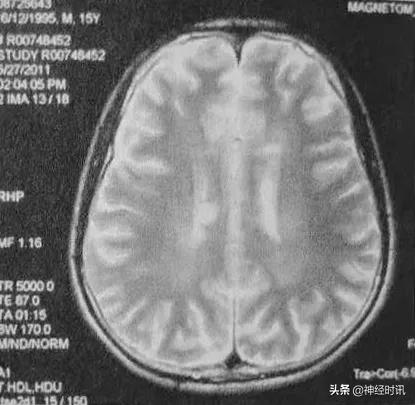

头部MRI(2011年5月):左侧半卵圆区、双侧侧脑室角及体旁白质、左侧额叶颞叶皮质下、右侧脑干缘可见斑片状及斑点状常T2信号影,无强化。

临床诊断上,除了McDonald2010年诊断标准(现已更新至McDonald2017年诊断标准)外,MRI也具有十分重要的重要。结合上述病例,该患者头部MRI中有多发的白质部分病灶,颈部MRI中可见单个椭圆形病灶,边界清楚。